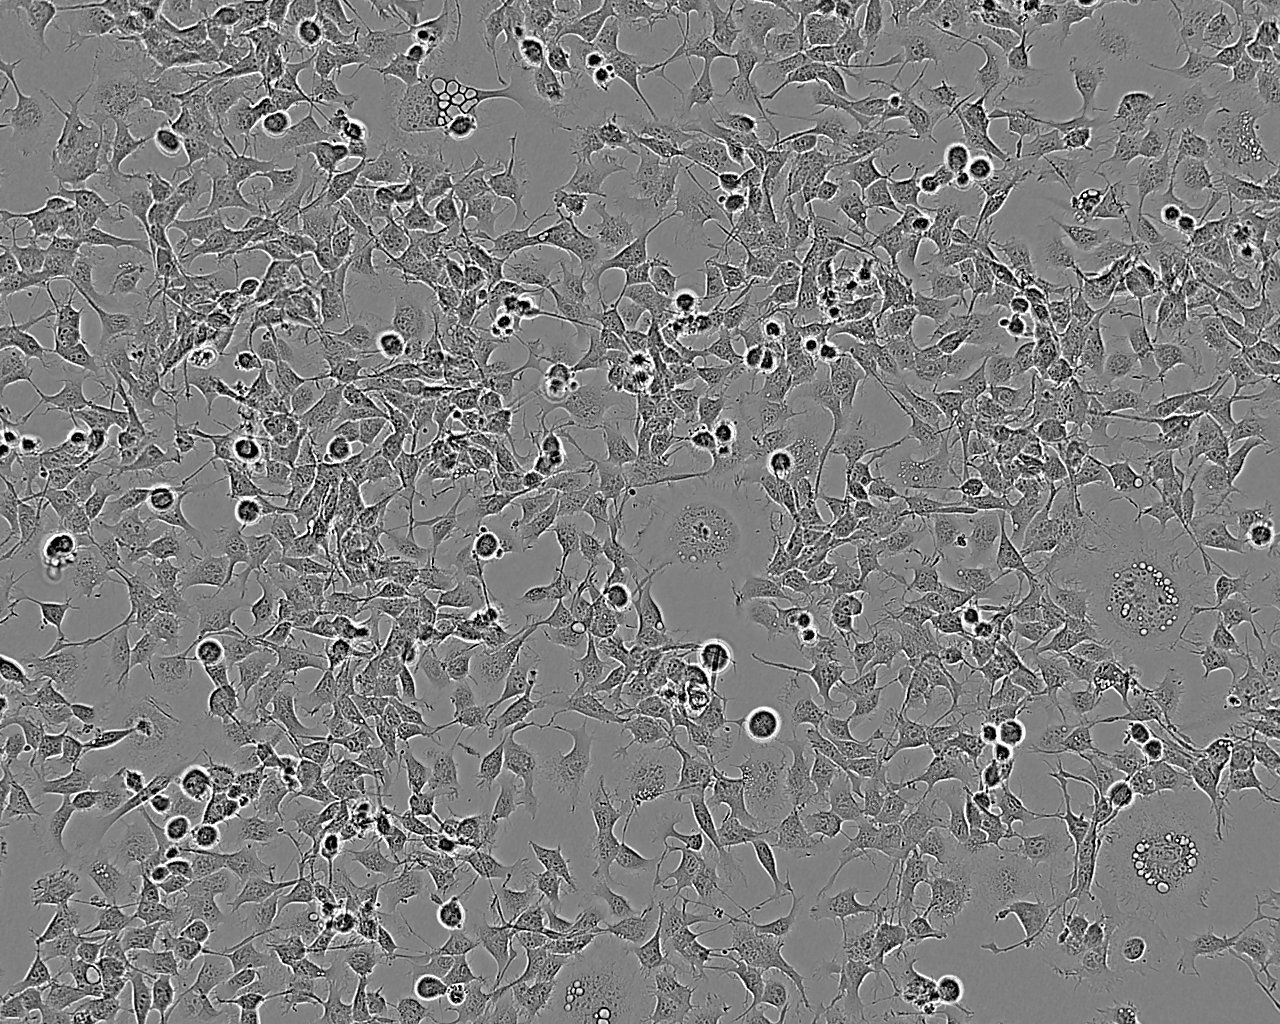

LAPC-4 cell line人前列腺癌细胞系

LAPC-4 cell line

细胞背景资料:前列腺癌;淋巴结转移;男性

细胞形态:上皮细胞样

细胞生长:贴壁

细胞物种来源:人源或鼠源等其它物种来源

细胞产品包装:复苏形式:T25培养瓶(一瓶)或冻存形式:1ml冻存管(两支)

细胞传代方法:1:2-1:3传代;每周换液2-3次。

细胞生长特性:贴壁